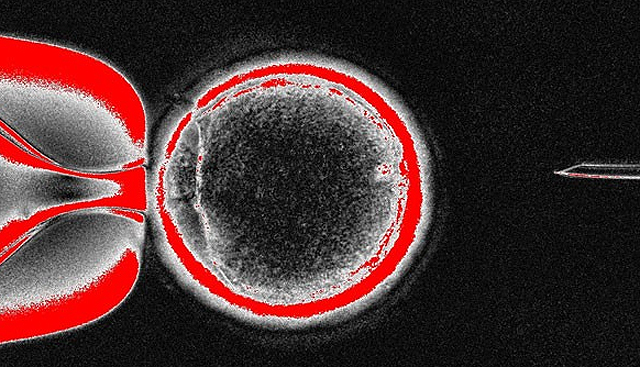

Com sede em Nova Jersey (leste), a empresa NeoStem investiga células muito pequenas similares às embrionárias. Estas células, chamadas VSEL (very small embryonic-like cells, em inglês), foram encontradas na medula óssea de um adulto e, segundo esta empresa, provavelmente podem se regenerar em vários tipos de tecidos.

A pesquisa gerou polêmica na comunidade científica pelo acordo de marketing existente entre a NeoStream e o Vaticano, e também porque três estudos independentes não conseguiram confirmar a existência das células VSEL. O último financiamento recebido pela NeoStream de parte do Instituto Nacional de Saúde dos Estados Unidos (NIH, na sigla em inglês), foi aplicado para em um tratamento experimental com VSEL para regenerar tecidos danificados pela periodontite, uma doença que afeta as gengivas.